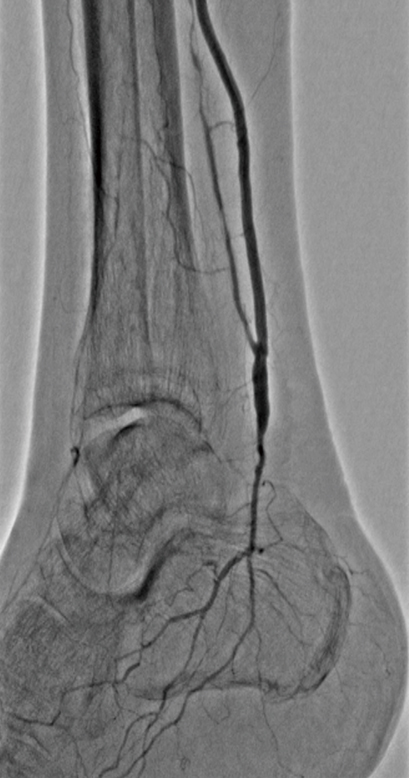

Vascular Surgery下肢閉塞性動脈硬化症

血管造影検査 など

血行再建術

外科的治療と血管内治療があります。外科的血行再建には動脈バイパス手術や血栓内膜摘除が含まれます。血管内治療はバルーン血管拡張術やステント留置術があり、循環器内科で行っています。患者さんの重症度や病態に応じて、循環器内科と協議して最適な治療法を選択しています。

デジタル血管造影装置つきハイブリッド手術室